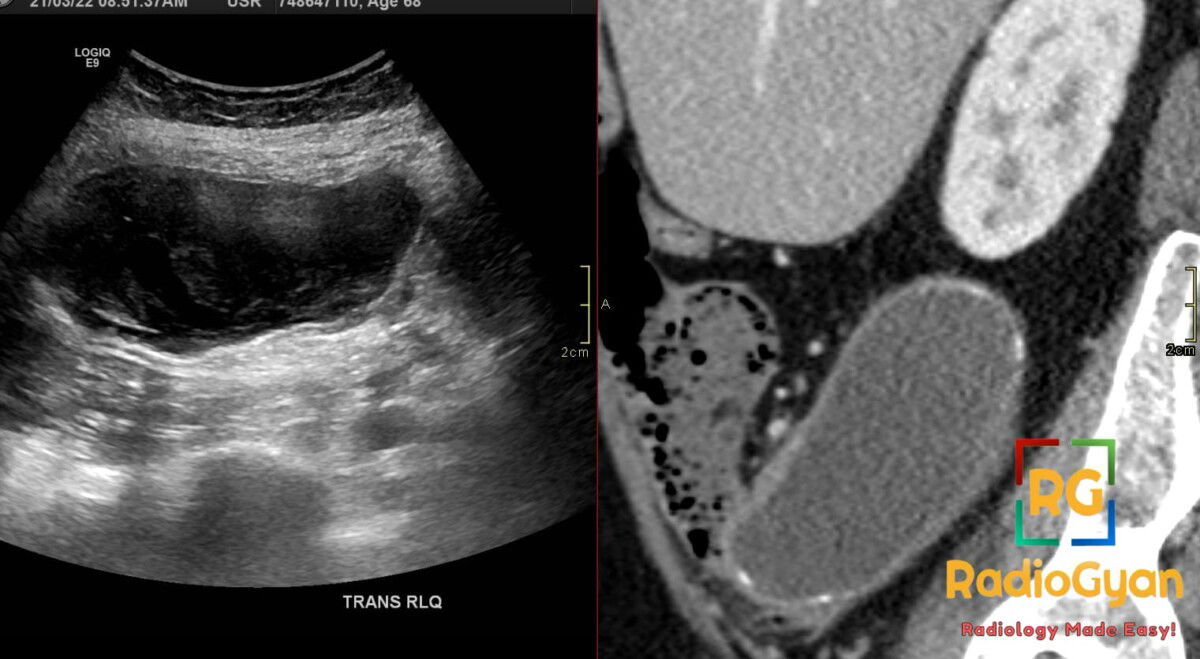

62 yr female presenting with a palpable right lower quadrant mass and chronic abdominal pain.

Diagnosis: Appendiceal Mucocele

- Characterized by an appendiceal outer-to-outer diameter of 15 mm or greater, which is the diagnostic threshold to distinguish it from acute appendicitis.

- The “Onion-skin sign” on ultrasound is considered pathognomonic, representing multiple echogenic layers of inspissated mucin.

- Wall calcification on CT is highly specific for the diagnosis, though present in less than 50% of cases.

- US: Elongated tubular mass in the right lower quadrant; characteristic “onion-skin” texture with internal echogenic layers; “drumstick” or “pear-shaped” appearance; no internal blood flow on Doppler; mucinous ascites from rupture appears as low-level echoes with ill-defined septations.

- CT: Round or tubular low-attenuation (17-26 HU) cystic mass near water density; well-encapsulated; wall calcification is a strong diagnostic feature; wall irregularity and mural nodularity suggest malignancy (cystadenocarcinoma).

- Signs: Onion-Skin Sign: Pathognomonic ultrasound finding of multiple echogenic layers; Whorly/Onion Peel Appearance: CT description of layered mucin within the dilated lumen.